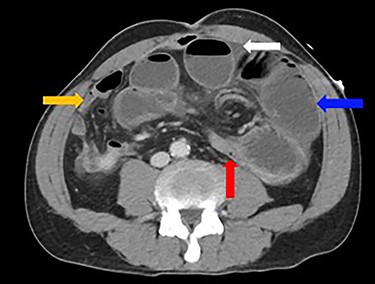

Dilated loops of small bowel (blue arrow), oedematous mesentery (suggestive of closed-loop obstruction; red arrow), free fluid (evidence of CA; white arrow) and collapsed small bowel (orange arrow)

A 52-year-old man presented with a 1-day history of generalized abdominal pain, distension and vomiting. Two years prior, he underwent a subtotal colectomy for colorectal cancer associated with Lynch syndrome and adjuvant chemotherapy. He was haemodynamically stable on presentation. Examination revealed a soft abdomen with marked distension and left periumbilical tenderness, however, no peritonism. Biochemistry showed lactate: 1.9, white cell count: 17 and C-reactive protein: 10. Computed tomography (CT) abdomen demonstrated a closed-loop SBO with transition point mid-abdomen, free fluid but no free gas (Figs 1 and 2). The patient was resuscitated with intravenous fluids, a nasogastric tube was inserted and they proceeded to an exploratory laparotomy for the closed-loop SBO. Intra-operative findings noted a loop of distended small bowel adherent to the anterior abdominal and pelvis side walls, with a loop of ileum twisted at the mesentery secondary to a band adhesion causing the closed-loop obstruction. The patient underwent adhesiolysis and untwisting of the mesentery, which demonstrated viable ileum with no evidence of perforation. In addition, the liver was smooth, there was no evidence of peritoneal metastases and the previous side-to-side ileo-sigmoid anastomosis was intact with no evidence of stricture or cancer recurrence. Lastly, milky intra-abdominal fluid was noted intra-operatively, with a sample sent for biochemistry showing a triglyceride level of 1584 mg/dl indicative of CA. Post-operative recovery was delayed by a prolonged ileus for which they were commenced on total parenteral nutrition (TPN) and slowly upgraded to a low-fat diet following resolution of the ileus. They were discharged home on Day 49 post-operatively.